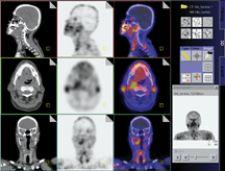

GE Healthcare's Discovery STE clinical imaging assists with diagnosis.

Image fusion — combining image data from different modalities, and of which hybrid imaging is a subset — is revolutionizing the way physicians view and treat disease. The process can be performed through computer workstations and software, however, dedicated hybrid systems, such as PET/CT and more recently, SPECT/CT, minimize the drawbacks of fusing images derived from two separate pieces of equipment. According to some experts, dedicated hybrid systems possess the potential to bring the diagnosis and treatment of cancer, neurological and cardiac diseases to the brink of transformation. These hybrid units, which allow the patient to remain on the same exam table for both scans, produce almost perfectly aligned images, leading to earlier, more accurate detection and treatment and, ultimately, better patient outcomes.

By 1994, when PET physicist David Townsend, Ph.D. and Ronald Nutt, Ph.D. received a grant from the National Institutes of Health (NIH) to build the first PET/CT prototype, PET was already recognized as an important diagnostic tool. Today, based on Drs. Townsend and Nutt’s collaboration, the ability to combine physiological data from a PET exam with CT’s anatomical image slices has made PET/CT the number one imaging tool in oncology, and its potential for other clinical applications is growing. Over 1,000 PET/CT systems are currently in clinical use, said Dr. Townsend. Results of PET/CT scans not only enhance cancer detection, but also aid in the staging, treatment and follow-up of the disease, allowing physicians to personalize treatment plans.

“As data demonstrating the advantages of PET/CT over magnetic resonance and CT images in early disease detection continue to accumulate, it is reasonable to anticipate that PET/CT imaging systems could become the ‘first line of defense’ in optimization of treatment for cancer patients,” according to Jacqueline Brunetti, M.D., director of Radiology, Holy Name Hospital, Morristown, NJ.